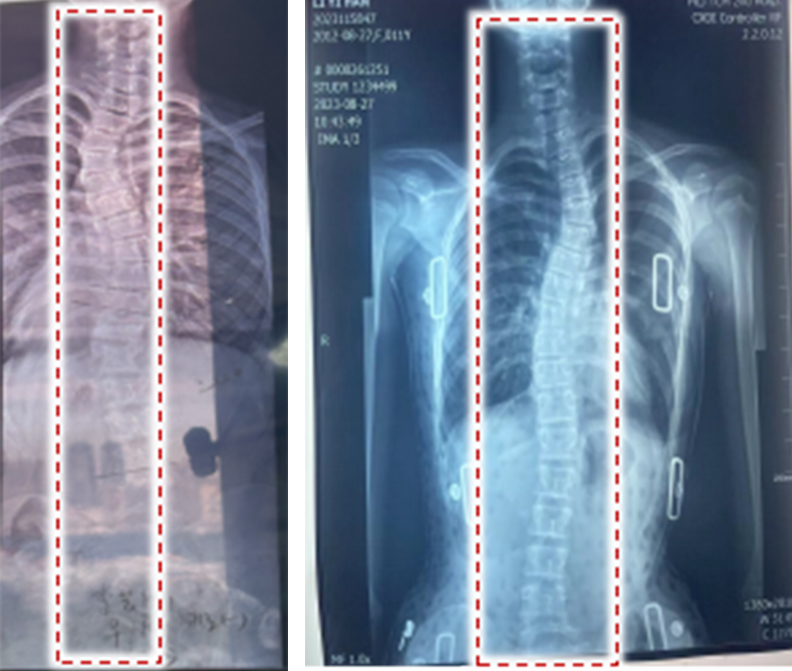

4D-printed intelligent orthotic devices can be worn on human limbs, trunks, and other body parts to prevent or correct physical deformities and related disorders. These devices feature personalized design and customization.

By virtue of their shape memory performance, they enable free adjustment and progressive correction after structural forming, and boast advantages such as precise reduction, rapid fabrication, easy donning and doffing, as well as cost-effectiveness and accessibility.